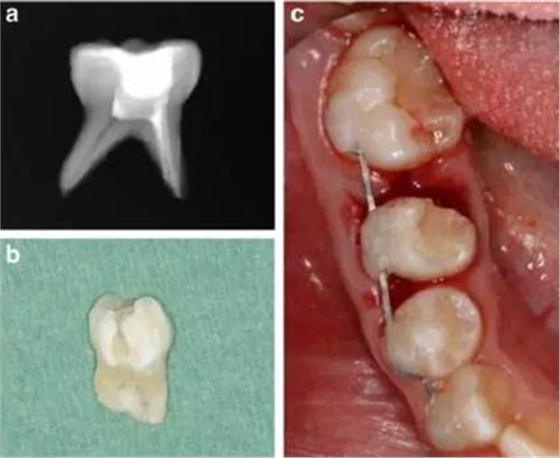

牙槽固連技術包括在局麻下拔除乳磨牙,然后進行近中根的體外根管治療,對牙冠做復合樹脂的修復,進行2mm的根尖切除術和偏側牙根切除。為了達成牙槽固連,我們采用了根尖孔閉合且在口外干燥60分鐘以上脫位牙的處理方法。用刮治器從根面上收集牙周膜細胞。拔除6分鐘后,用鹽溶液沖洗牙槽窩,將近中牙根帶輕微壓力重新植入。為了保持牙齒穩(wěn)定,從右側尖牙到右側第一磨牙應用0.016’’*0.022’’不銹鋼方絲作為牙弓夾板。